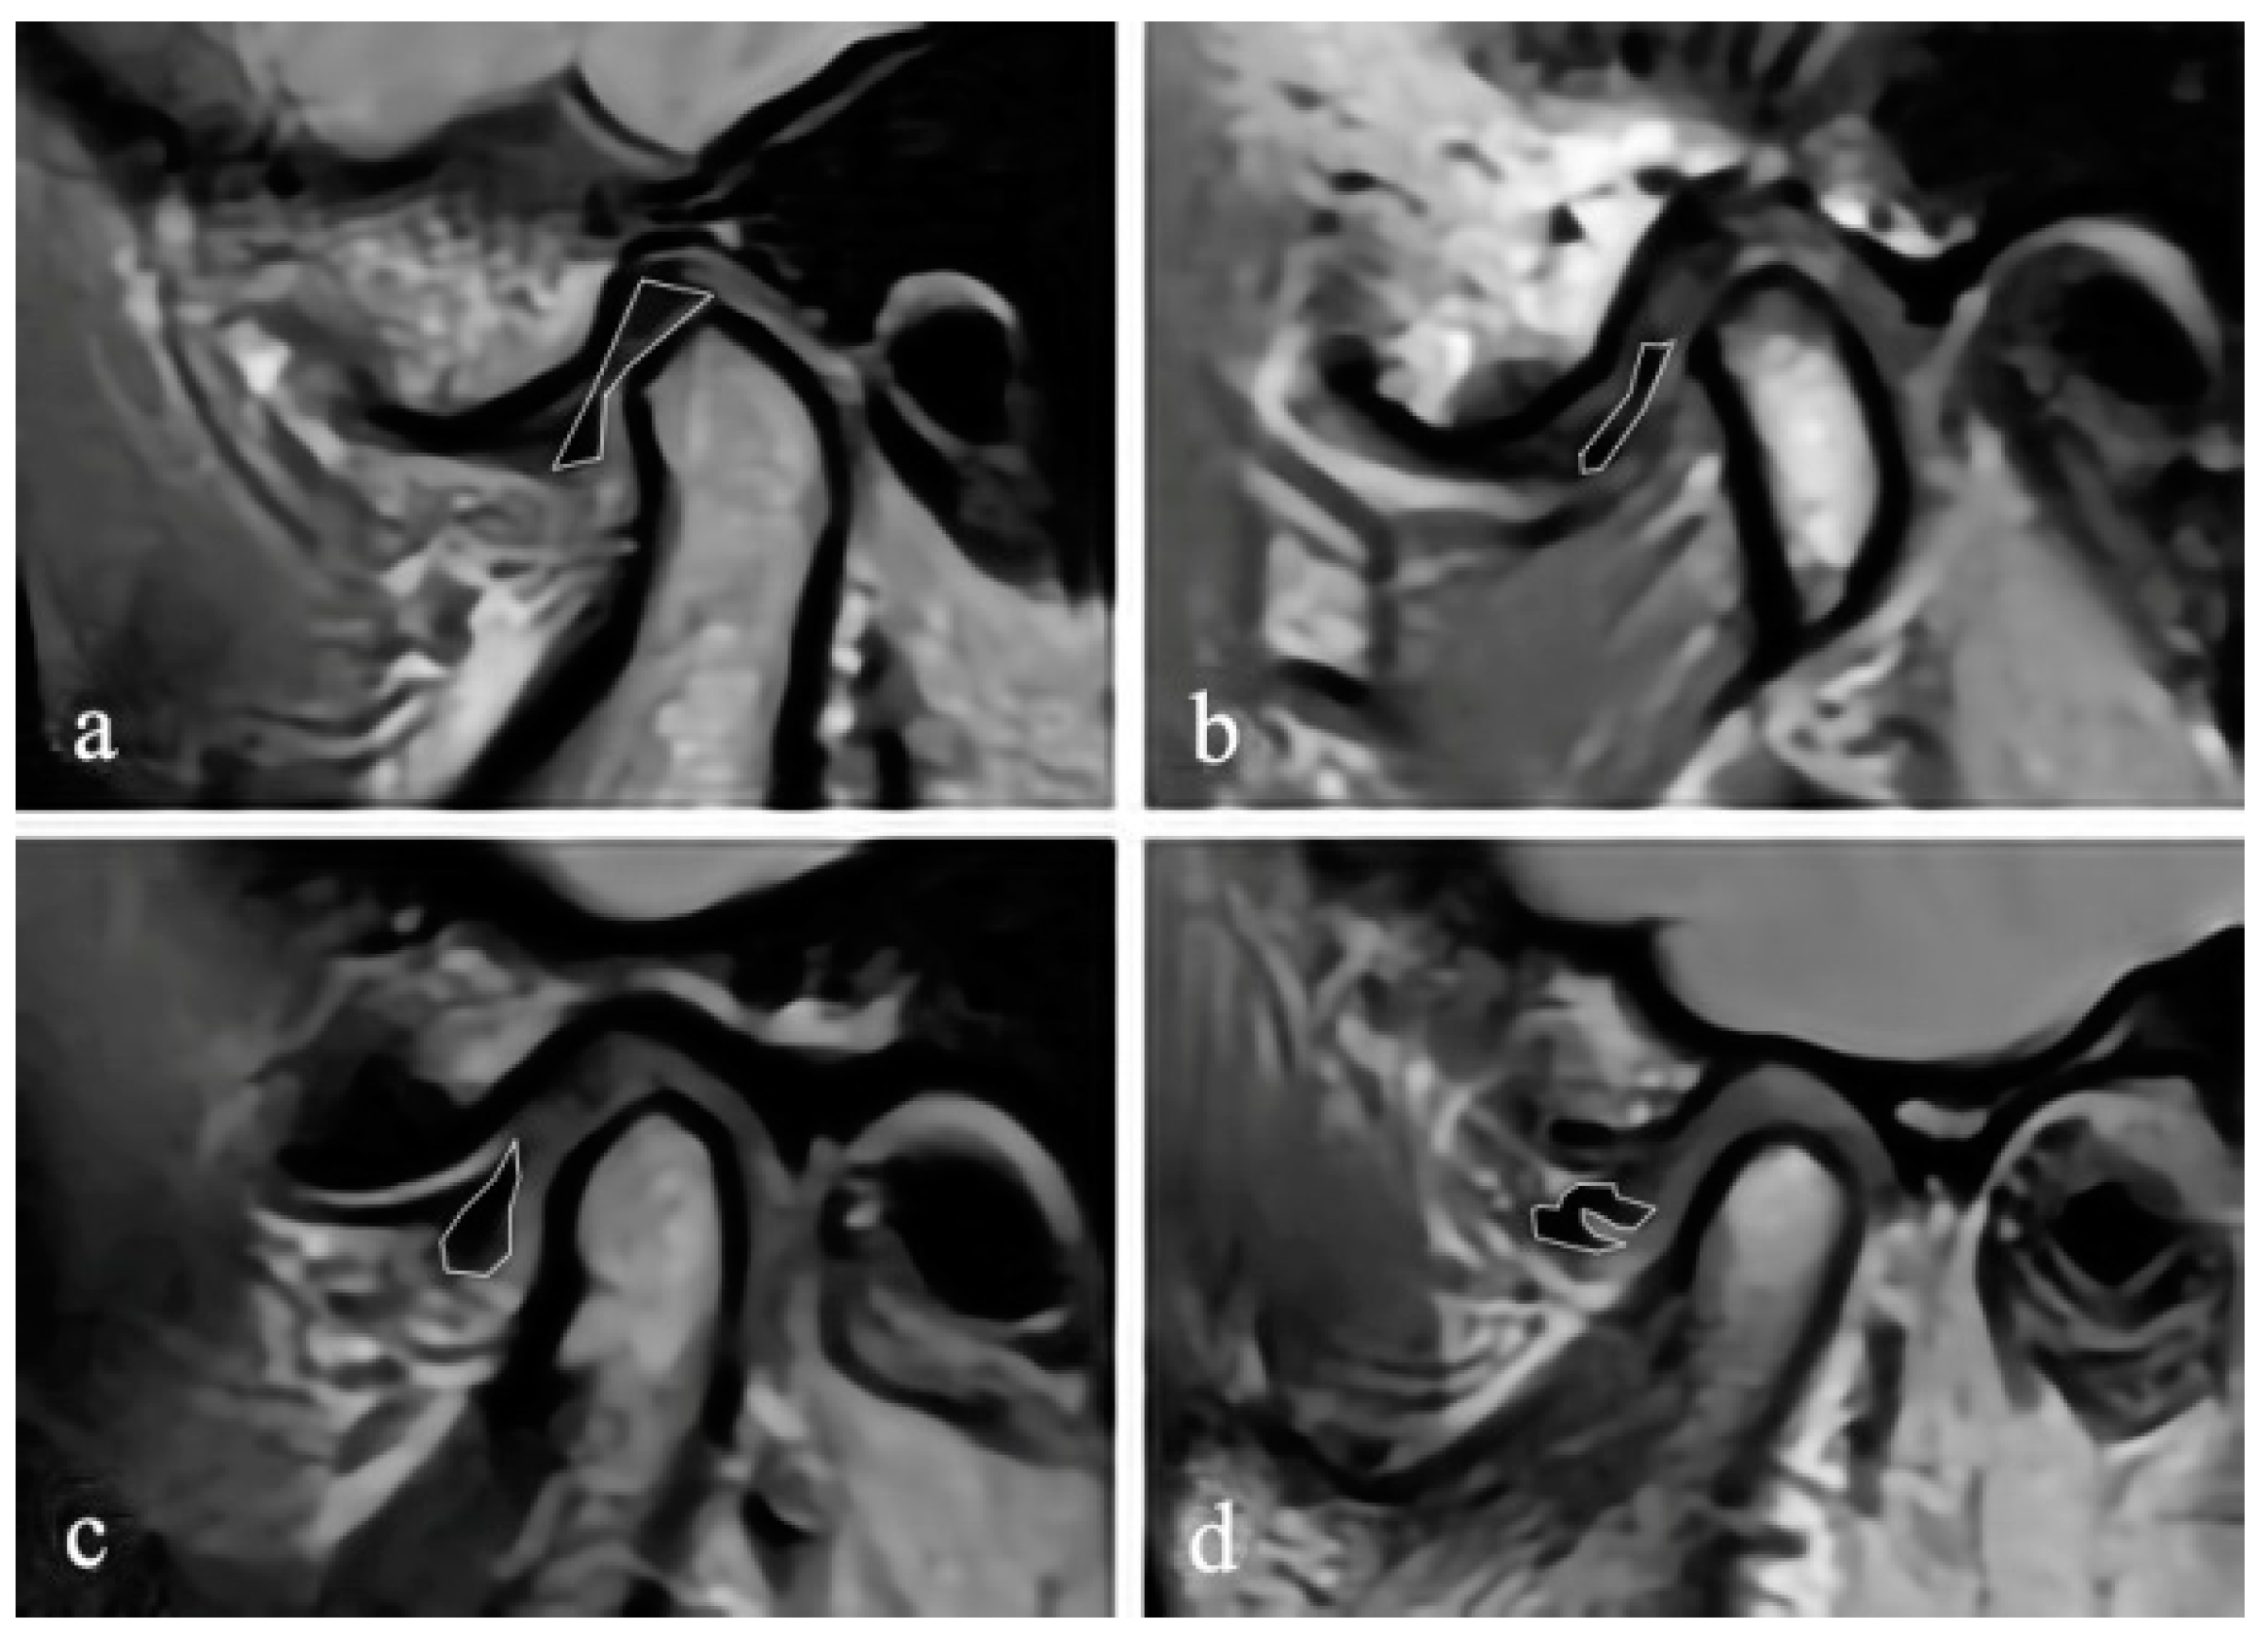

The authors evaluated the condyle and the joint spaces on the CBCT images. The sagittal and coronal images were reconstructed by an axial view showing the maximum mediolateral dimension of the condyle. The slice thickness was 1 mm. On the reconstructed CBCT images, as described by Ahmad et al., the surface of each condyle was classified as normal, flattening, erosion, osteophyte, subcortical sclerosis, and subcortical cyst [20]. Each possible change could appear alone or in combination in at least two sequential parasagittal sections. Considering that the increase of the diagnostic types may result in reduced reliability, we combined the types that were less common into one category for statistical purposes. The superior space (SS), posterior space (PS), and anterior space (AS) of joints were measured on the middle layer of the reconstructed sagittal images. The parameter of PS/AS was calculated to assess the anteroposterior relationship of the condylar to the fossa. Additionally, coronal images were also used to determine the position of the condyle. On the middle layer of the reconstructed coronal images, the lateral space (LS), central space (CS), and medial space (MS) were measured using the method of Ikeda [21] (Figure 3).

Figure 3. (a) The measurements of the lateral space (LS), central space (CS), and medial space (MS), and (b) the measurements of the anterior space (AS), superior space (SS), and posterior space (PS).